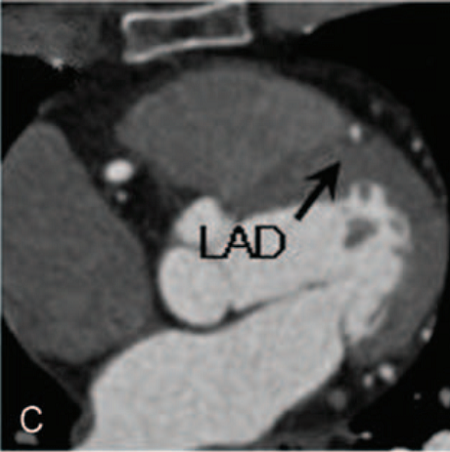

青年男性,34岁,反复胸部针刺样疼痛及头晕1年。除低血压和"神经衰弱"之外,既往无特殊病史,不抽烟、酗酒,无心脏病家族史。患者年轻的时候身体虚弱。入院时血压110/70 mmHg,心率72次/分,体检无特殊。心电图和胸部X光显示正常。但超声心动图却有重大发现,提示左心室壁乳头肌水平以下小梁增加,心内膜壁深层交界凹陷,特别是在心尖部游离壁(图A),其小梁厚度为9mm,心肌变得更薄;心尖搏动减弱,二尖瓣见血液反流(图B),LVEF 57%。冠脉CTA显示左前降支(LAD)心肌桥,长度为38.9 cm(图C、D),余冠脉未见明显异常。

图C、D 左前降支见心肌桥,长度为38.9 cm